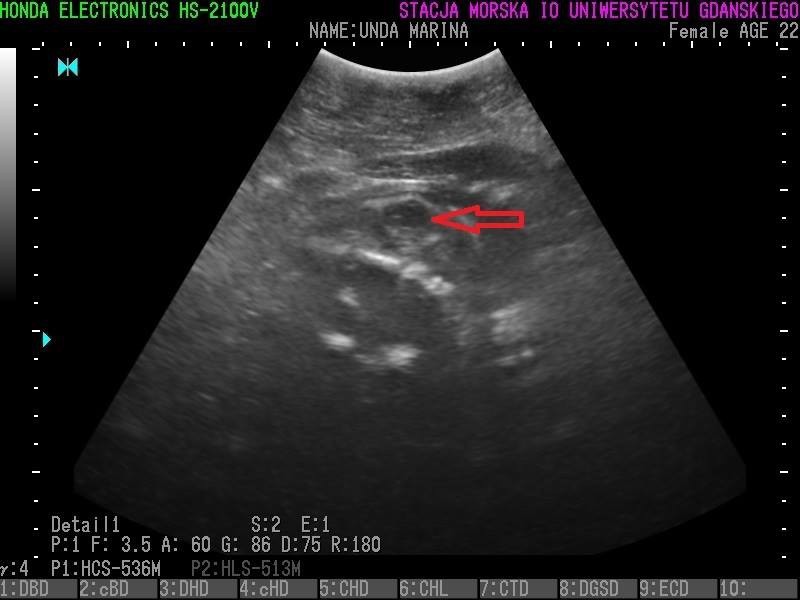

Wszystkie helskie foki - czyli Agata, Ewa, Unda Marina i Ania - są w ciąży. To wyniki badań ultrasonograficznych, które przeprowadzono w miniony piątek (23 grudnia).

• Z radością więc informujemy, że tego roku wszystkie nasze cztery samice spodziewają się potomstwa - czytamy na profilu Fokarium.

Szczenięta urodzą się najprawdopodobniej w marcu 2017 roku.